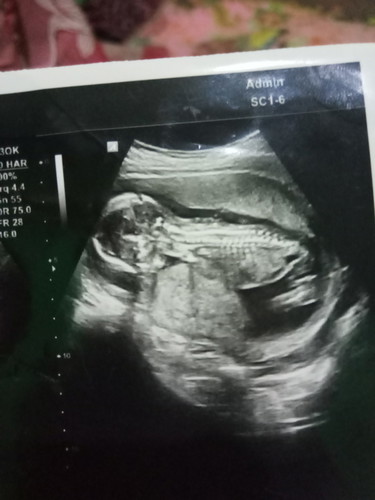

4 bulan baby boy

Sempat panik soalnya banyak orang bilang perut ku keci terus saya sering worry karena naik motor terus . Tp semalam pas USG puji tuhan bayinya sehat dan baby nya cowok . Tuhan senang banget . Kata dokter boleh naik motor yang penting hati" ? . Jadi bun kalau ada yang bilangin perutnya bunda kecil ya abaikan aja bun yang pentinh baby nya sehat ya bun